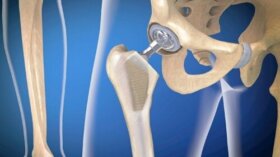

관절 보철물 감염은 관절 치환술 후 상대적으로 빈번한 합병증이다. 보철물 배치는 오늘날 뼈 장치와 관련된 수많은 병리를 치료하는 데 도움이…